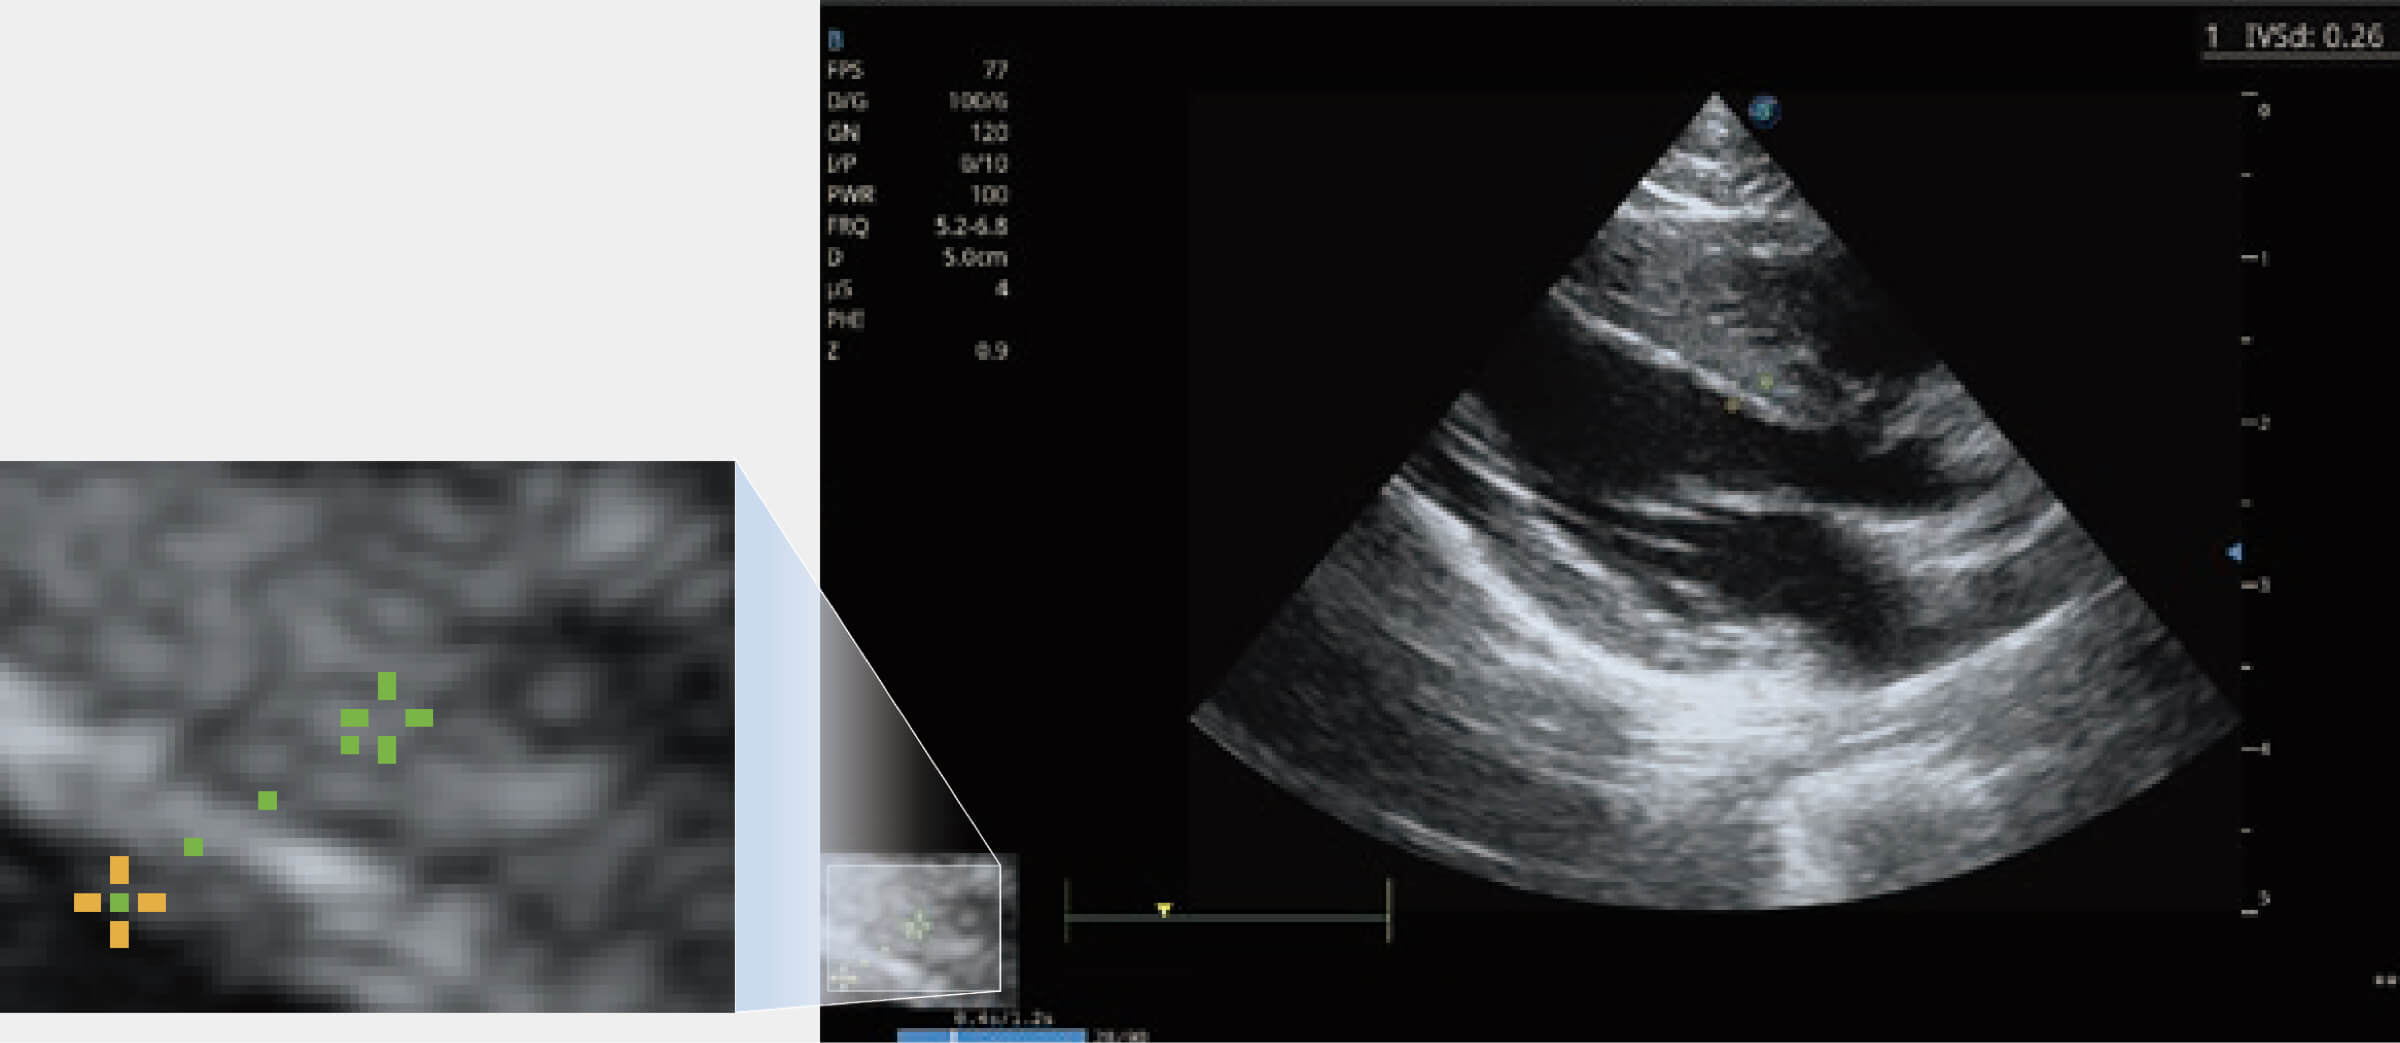

通過360度任意調(diào)節(jié)3條M型取樣線,在同一心動周期上觀察心臟不同位置的運(yùn)動曲線,得到準(zhǔn)確的心功能測量數(shù)據(jù),有效評估心肌運(yùn)動及左心室功能。